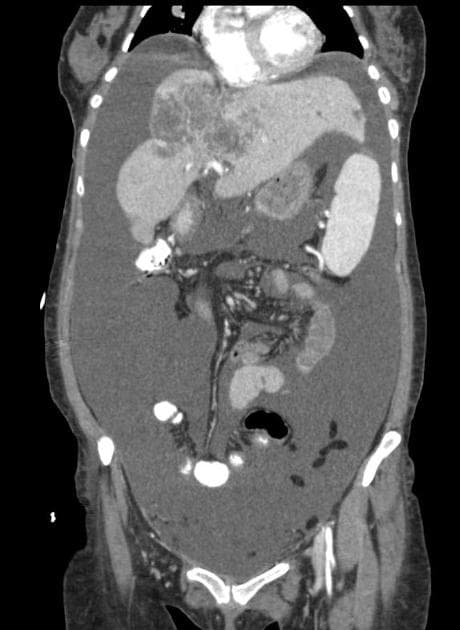

- Huyết khối lan tỏa ở tĩnh mạch mạc treo ruột trên và các nhánh lớn của nó, lan lên tĩnh mạch lách và tĩnh mạch cửa, bao gồm nhánh phải của tĩnh mạch cửa và đoạn gần nhánh trái.

- Các đoạn ruột non dày thành, phù nề và giảm tưới máu (hypoperfused), gợi ý thiếu máu cục bộ ruột non (small bowel ischemia).

- Ghi nhận giảm tưới máu ở thùy gan phải do huyết khối nhánh tĩnh mạch cửa phải, dẫn đến hiện tượng khác biệt tạm thời về tỷ trọng gan (transient hepatic attenuation differences – THAD).

- Dạ dày giãn, chứa dịch.

- Dịch tự do ổ bụng mức độ nhẹ.

- Các hình ảnh học điển hình cho thấy huyết khối tĩnh mạch cửa và tĩnh mạch mạc treo ruột trên, hậu quả là thiếu máu cục bộ ruột non (small bowel ischemia).